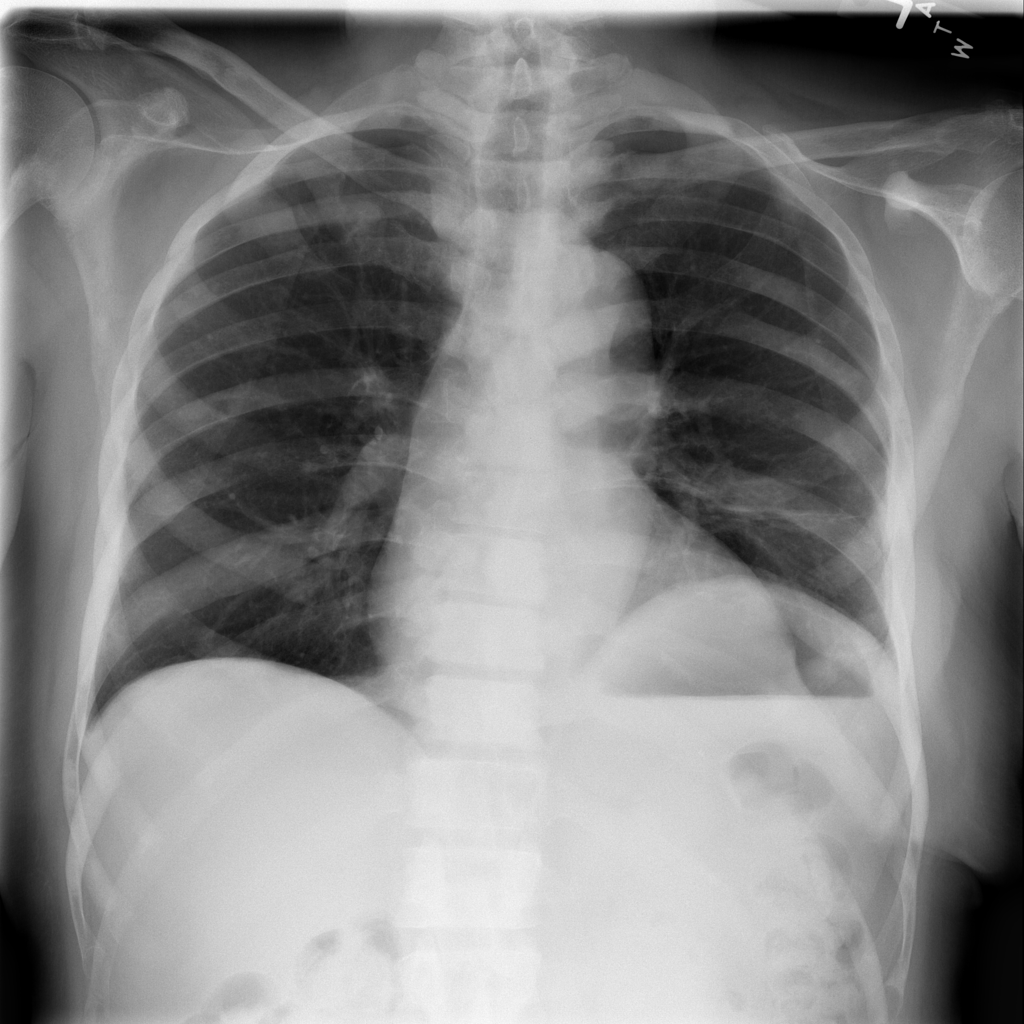

In this section we will show qualitative results of DINOv2 features using principal component analysis (PCA) performed on DINOv2 patch features on X-ray, CT, and MRI scans, following the method delineated in [8]. We will also provide organ segmentation results of linear compared U-Net decoders.

PCA visualization. Figure 2 shows the first three PCA components. The PCA is computed between patches of images that are in the same column, and the first 3 components are shown for X-ray, CT, and MRI scans. Thresholding is used on the first PCA component to remove the background. Just like in natural images [8], the colors of the three PCA components correspond well with the same parts of images in the same category. This is an easier task however, compared to natural images, because there is less variability between examinations on medical images compared to natural images.